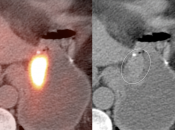

• Gastric Ulcer: May present as a small focus of intense uptake. Will require evaluation with upper endoscopy.

• Hiatal Hernia: Increased metabolic activity is frequently encountered within a hiatal hernia. Such uptake is nearly always physiologic or inflammatory. Malignancy, however, sometimes cannot be excluded and upper endoscopy may be required.